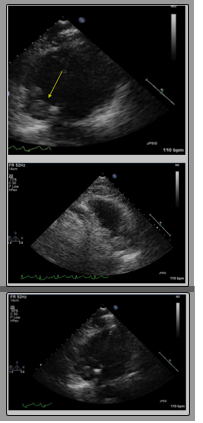

Then, the patient underwent a diagnostic paracentesis which showed a serum ascites albumin gradient (SAAG) of 1.9 and a fluid protein of 2.7 g/dL. Following the paracentesis, her mentation worsened, and she progressed to kidney and liver failure. The patient was empirically started on lactulose for suspected hepatic encephalopathy which improved her overall mentation. The patient’s renal function still continued to deteriorate throughout the course of hospital stay, despite treatment with IV fluids and albumin. The patient’s transaminase pattern now showed a mixed pattern of injury of both cholestatic and hepatic with an R factor 4. Treatment with IV fluids for acute renal failure worsened her diffuse edema and anasarca, so the patient underwent a therapeutic paracentesis with removal of 4 liters of peritoneal fluid. Afterwards, her transaminases showed a primary hepatocellular injury pattern with R factor 14. With alpha fetoprotein (AFP) levels of 1700, the diagnosis of HCC was confirmed as a value greater than 500 supports the diagnosis of HCC without further imaging. A transthoracic echocardiogram showed a bilobed mass in the inferior portion of the right atrium:

Magnetic resonance venography (MRV) which showed occlusion of right intrahepatic portal vein: